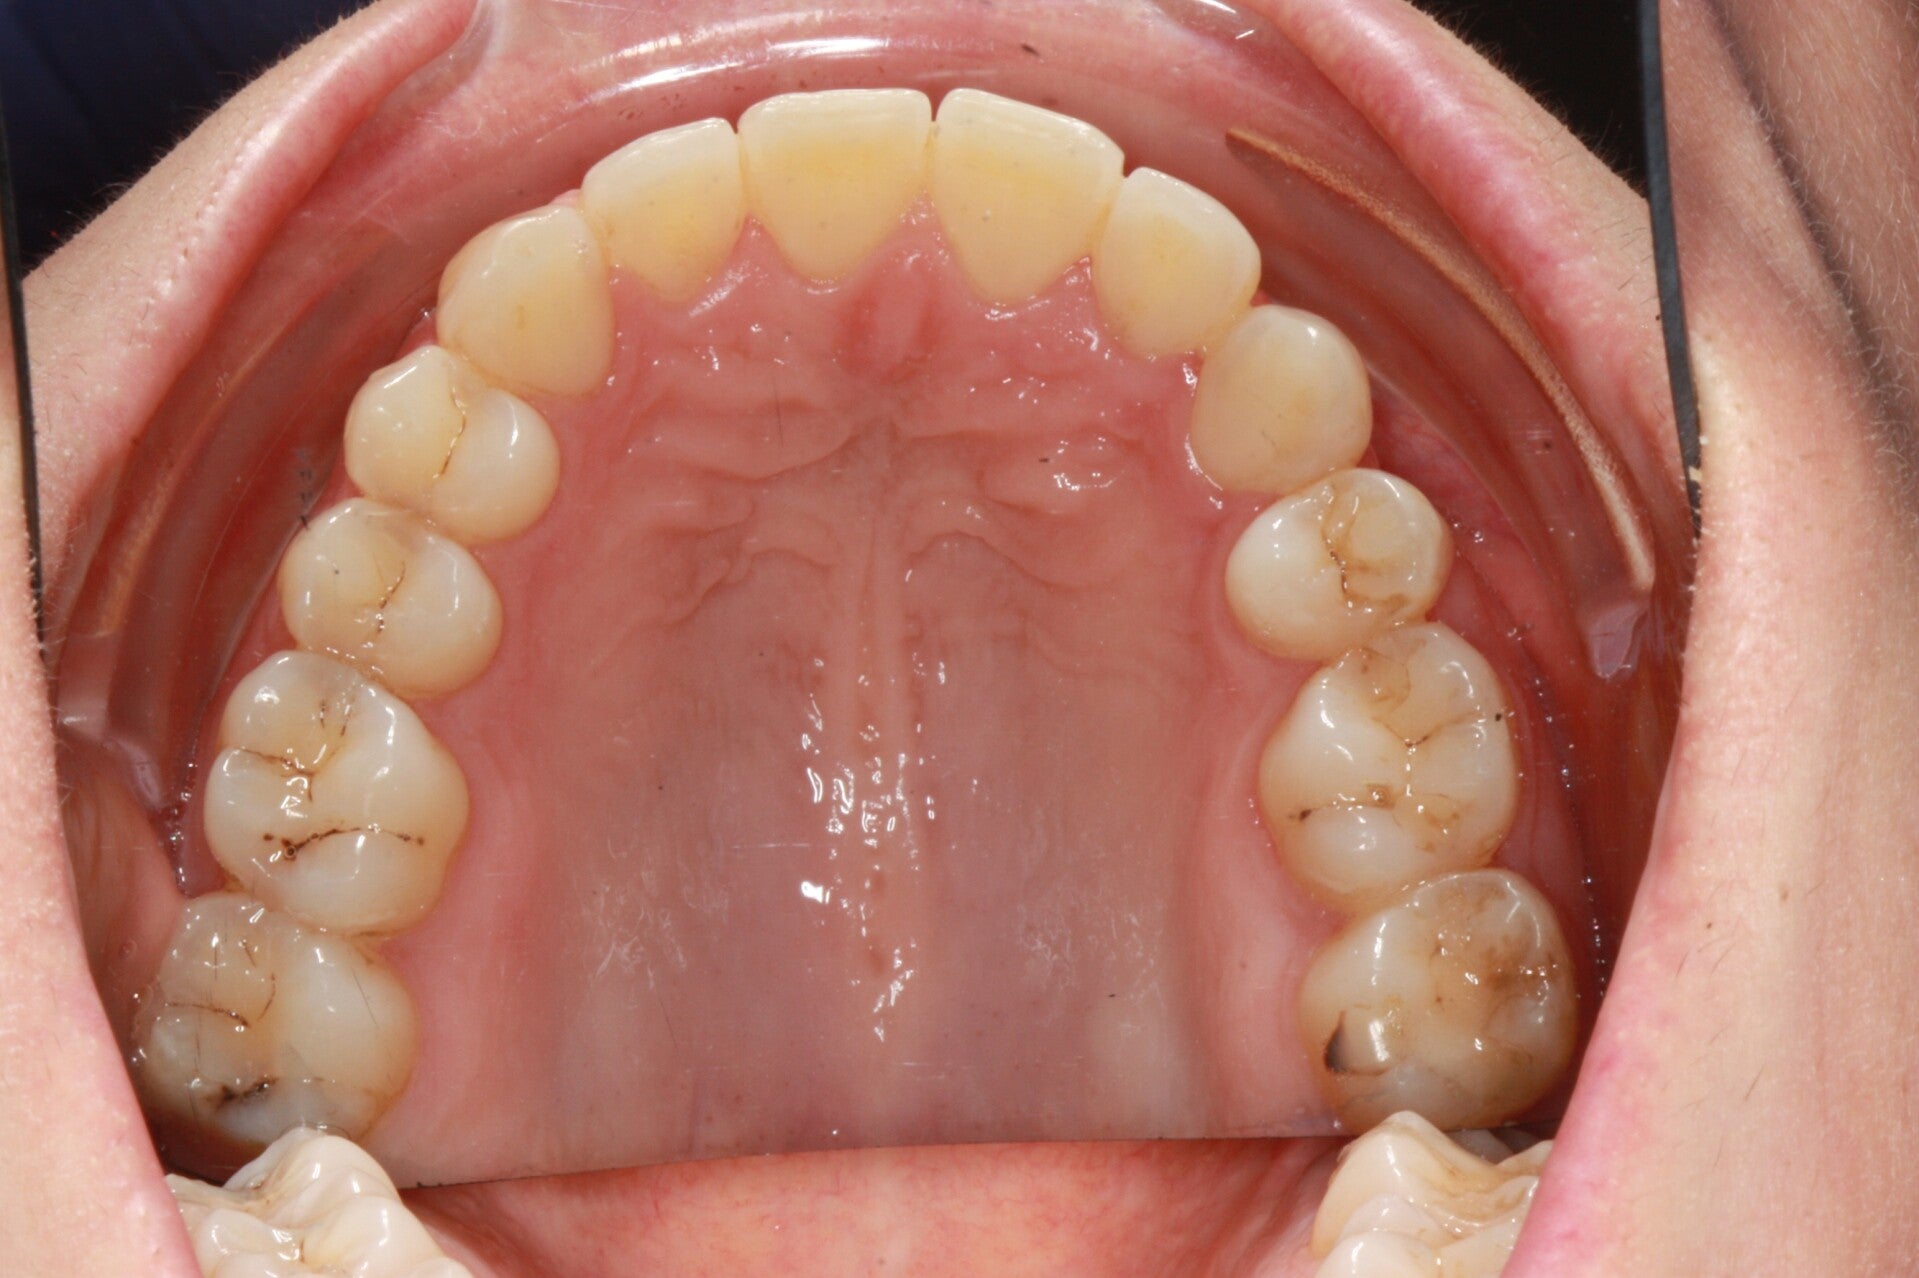

PRIMA CLASSE CON AFFOLLAMENTO GRAVE SUPERIORE A SINISTRA CON PERDITA PRECOCE DEL SECONDO MOLARE INFERIORE SINISTRO

Abbiamo appena portato a termine questo caso che presentava in arcata superiore il primo premolare di sinistra completamente fuori arcata sovrapposto al secondo premolare ed il canino ruotato.

in arcata inferiore invece abbiamo estratto il secondo molare di sinistra perso per carie deostruente e mesializzato il terzo molare in modo da chiudere lo spazio e non ricorrere all'inserimento di protesi implantare.